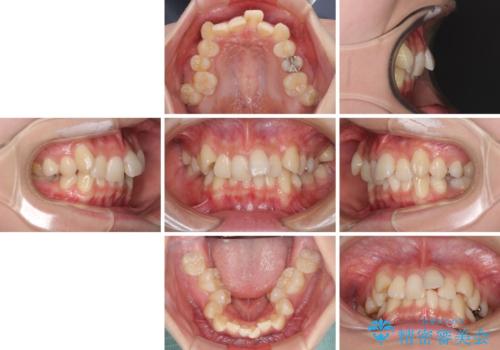

- 前歯の叢生と八重歯を気にして来院された患者様です。

叢生が強く、奥歯の咬合も左右差が大きかったため、上下左右4本を抜歯して、ワイヤー矯正を行うこととしました。

20歳前後と年齢が若かったため、非常にスムーズに歯列が整い、1年半をかけずに治療を終えることができました。